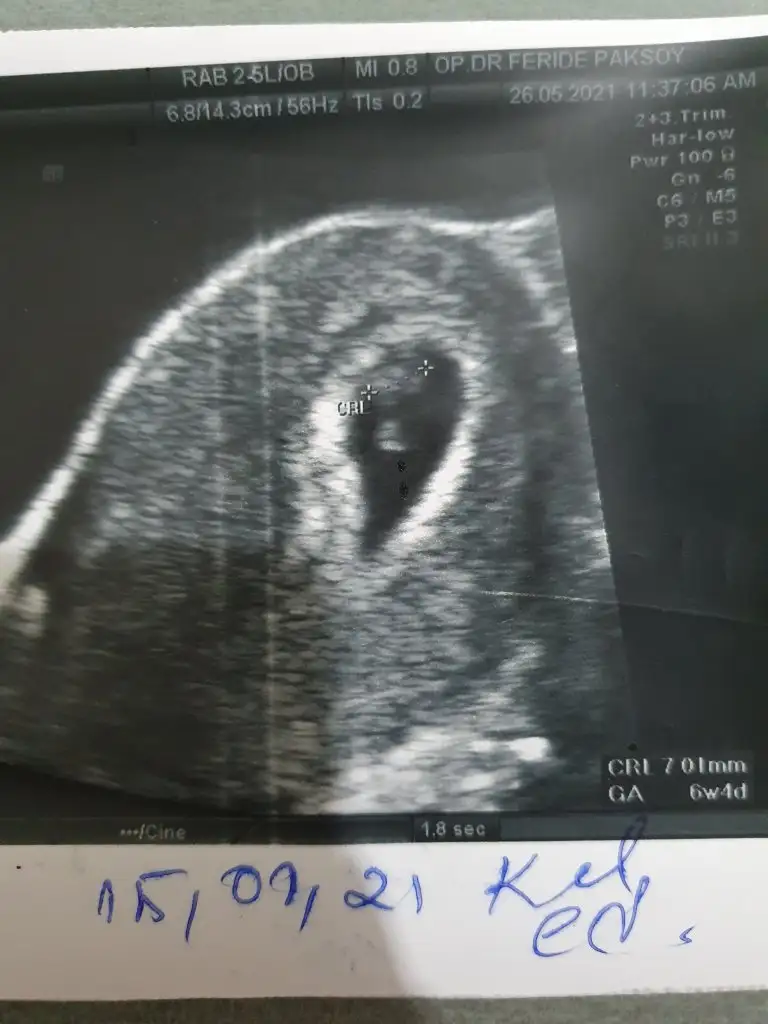

Merhaba 6+4 bana da bakar mısınız cok merak ediyorum. Karından bakıldı

Eklentiler

• 16222269650861797975188428297778.webp

30,8 KB · Görüntüleme: 599